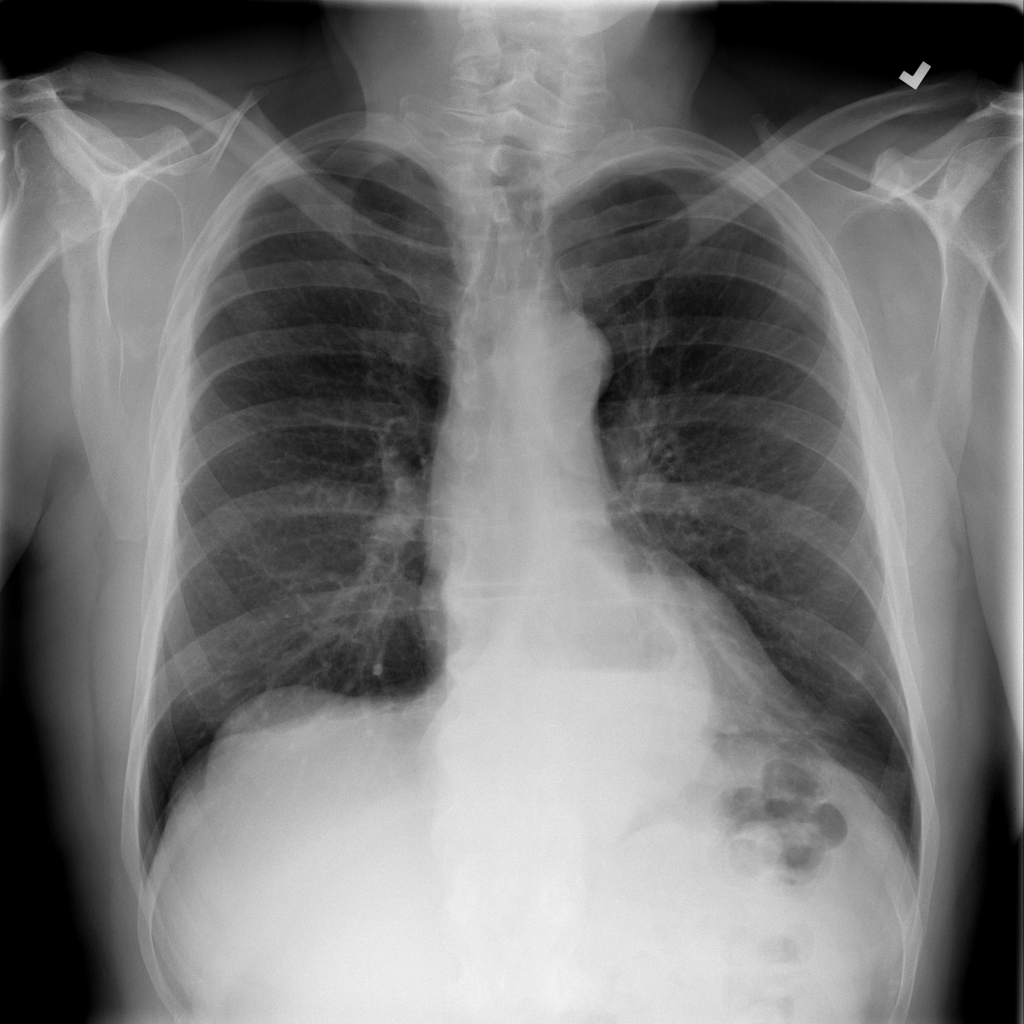

PAT-C048 · IMG-000Hernia

PAT-C048 · IMG-000

PA